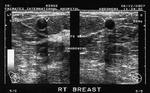

carcinoma breast with liver metastasis

This elderly lady has a solid markedly hypoechoic mass lesion in the right breast, just lateral to the nipple, in the upper lateral quadrant. Ultrasound images of this case show a well defined, non-calcific, mass, which is taller than it is wide and has an irregular contour. These are alarming findings and indicate a possible malignant mass of the right breast.

In addition, the liver shows multiple solid, rounded echogenic mass lesions scattered through both lobes of the liver.

Final diagnosis confirmed by FNAC - carcinoma right breast with liver metastases.